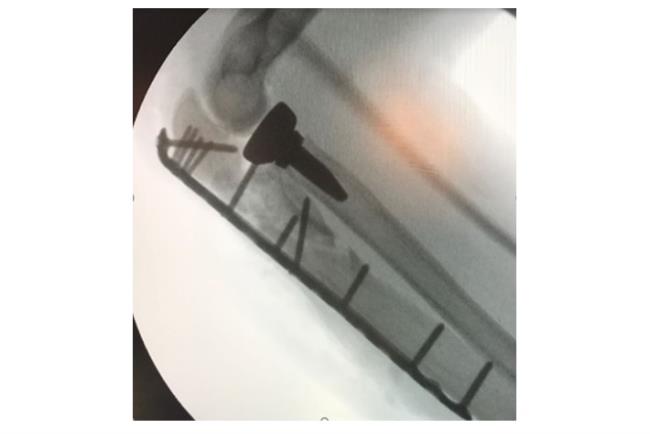

בשלב הראשון יתבצע צילום רנטגן. אם עולה חשד לכך שהשבר מערב גם את המפרק תתבצע גם בדיקת CT לשם הדמיה תלת ממדית של האזור הפגוע וחלקי השבר אותם יש להרכיב כדי להשיב למפרק את תנועתו התקינה. לרוב, כדי לטפל בשברים מורכבים יתבצע ניתוח ולא קיבוע בגבס.מטרת הטיפול בגבס היא קיבוע המצב הקיים ועל כן במקרה של שבר מורכב טיפול זה לא יועיל בהשבת התפקוד המפרקי. לכן, כדי להשיב את המצב לקדמותו יש צורך בפתיחת המפרק, העמדת כל אחד מחלקי העצם במקומו וחיבור החלקים אחד אל השני. הניתוח והקיבוע נעשים ע"י פלטות ברגים ומסמרים תוך לשדיים העשויים טיטניום או סוג של פלדת אל חלד.

קיבוע פנימי של המרפק | באדיבות פרופ' דורון נורמן